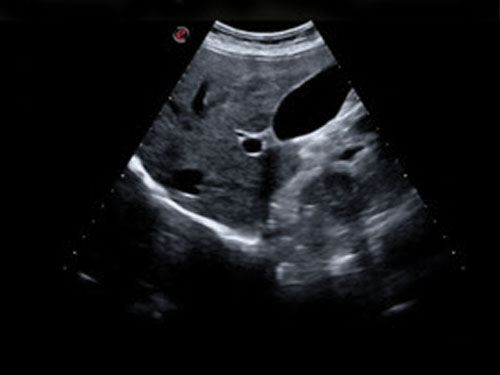

Nový produkt Esaote MyLab X7 od společnosti Esaote pokrývá všechny klinické aplikace. Od břišních po endokrinologické aplikace, stanovení diagnózy a poskytování nejlepší možné péče.

Esaote MyLab X7 je vybaven komplexní kardiologicko-vaskulární konfigurací. Jedná se o kompletní systém pro jakékoli kardiovaskulární ultrazvukové vyšetření s přizpůsobitelnými měřeními a reporty.

microV: Hemodynamické hodnocení s vysokou citlivostí a vysokým prostorovým rozlišením pro charakterizaci vaskularizace lézí ve všech klinických aplikacích, rychlé a neinvazivní.